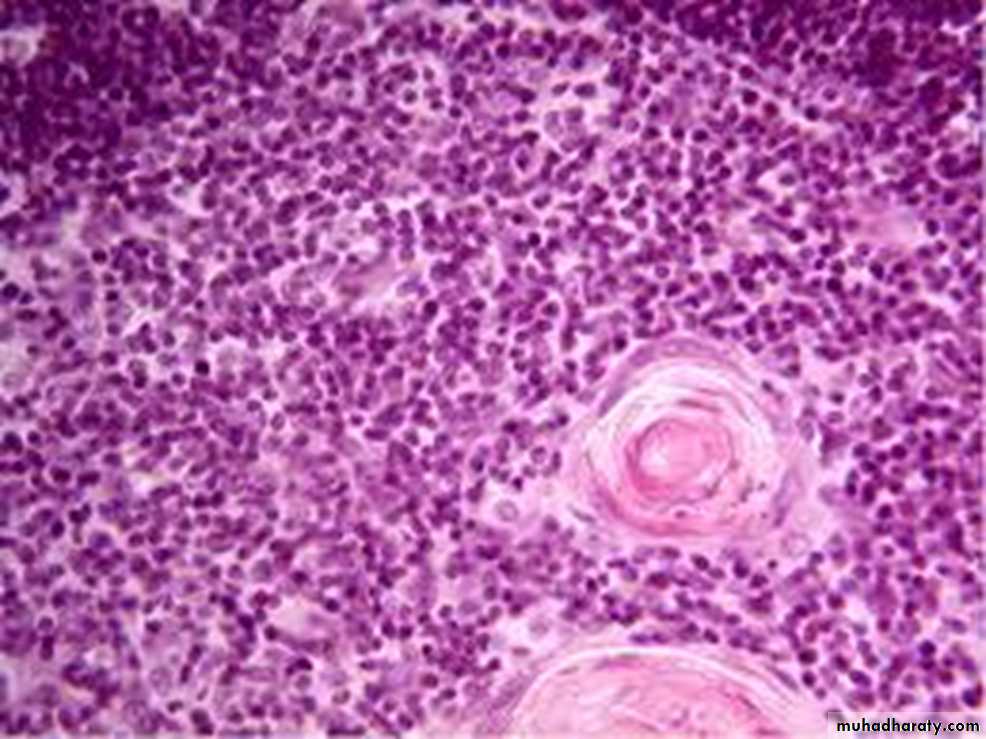

Hassal's corpuscles ( thymic corpuscles ):

It is spherical lamellated structures about 30-150 µm in diameter formed of central acidophilic hyalanized area surrounded concentrically arranged, flattened epithelial reticular cells that become filled with keratin filaments